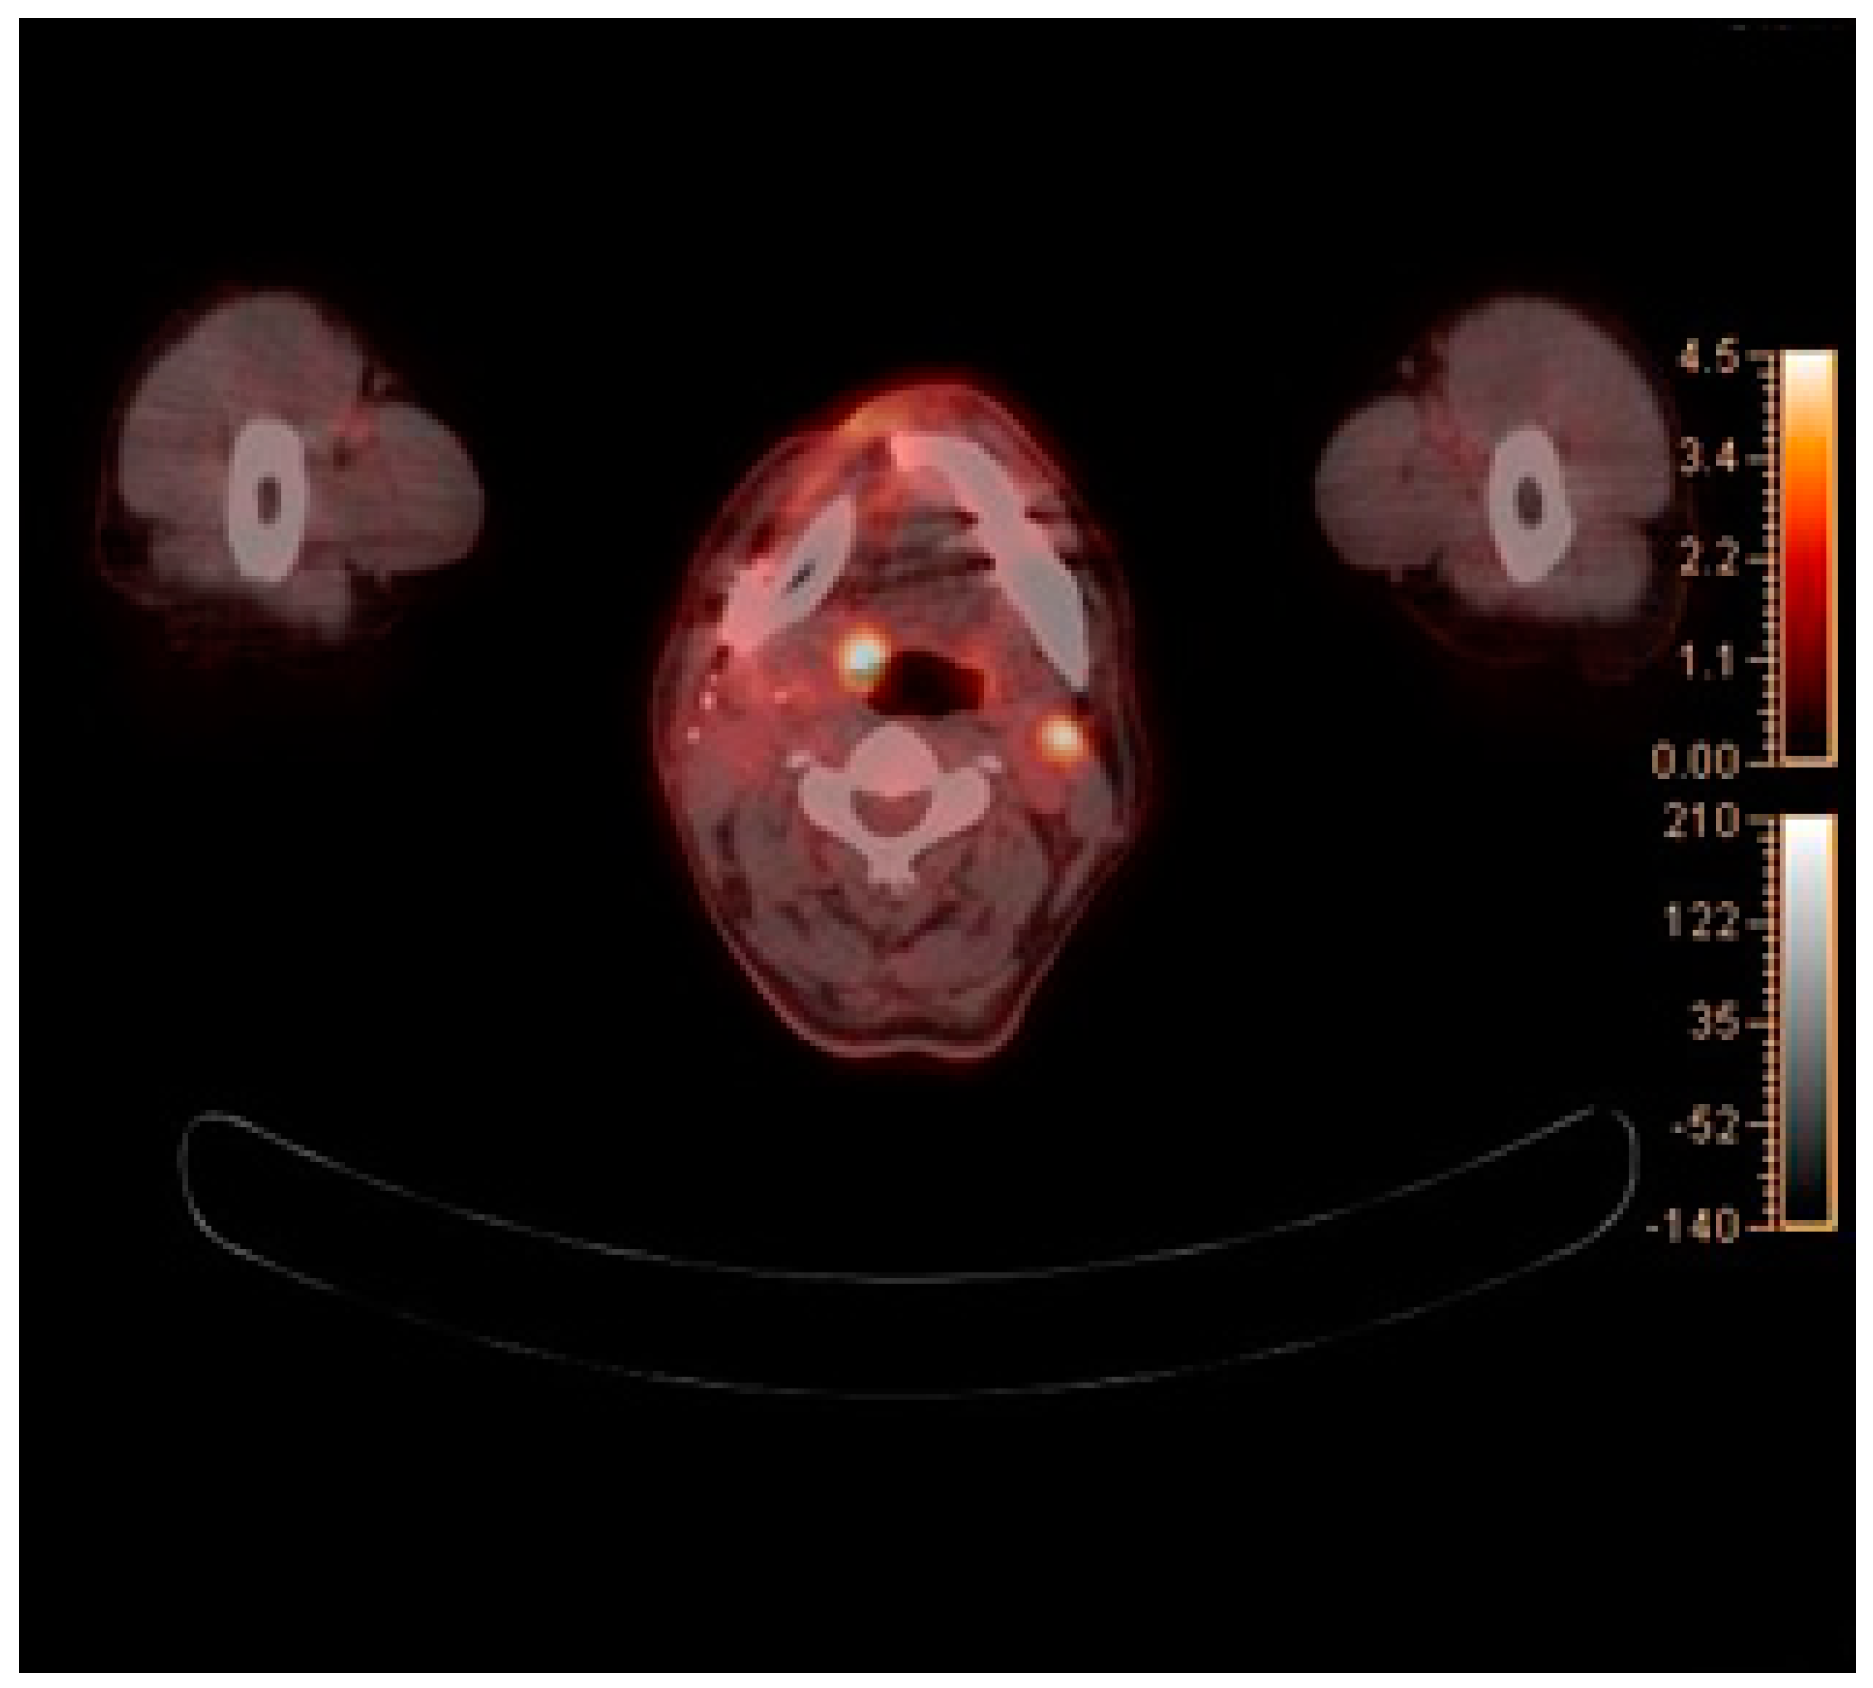

2. Case Report